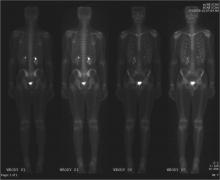

A new molecular imaging agent has been demonstrated to find prostate cancer that has spread to other tissues by locking in on the prostate specific membrane antigen (PSMA) enzyme, according to a new study. Results were presented at the 2015 Annual Meeting of the Society of Nuclear Medicine and Molecular Imaging (SNMMI).